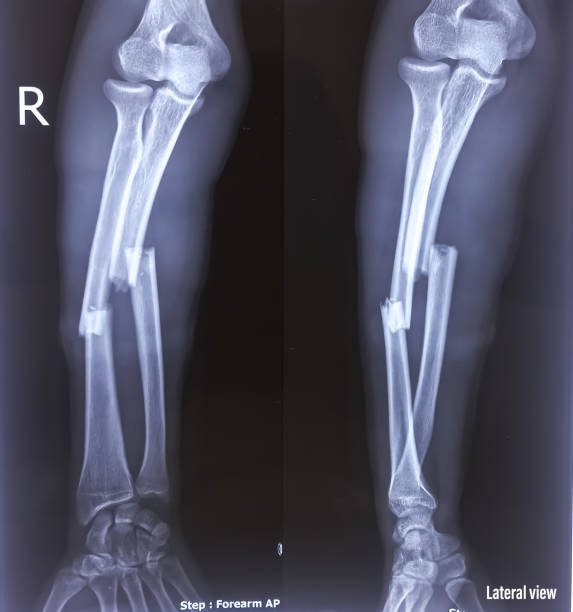

Osteomyelitis can be caused by either bacteria or fungi. One route of transmission is through the bloodstream. This occurs when there is an infection in the skin or muscle that is either untreated or ineffectively treated migrates to the blood. Another more common method of transmission is by injury or as a result of another disease like diabetes. A bone fracture especially an open fracture can also lead to osteomyelitis.

There are 2 types of osteomyelitis, acute or chronic osteomyelitis. Acute osteomyelitis occurs when the bone is infected with in 2 weeks of the original infection or injury. There are two ways acute osteomyelitis can develop, the most common is an injury to the bone, like with a fracture, or because of a primary disease like diabetes, this is called contiguous osteomyelitis. The other is when the infection is spread through the bloodstream, known as hematogenous osteomyelitis. This type usually affects young children, though it can develop in adults, especially an impaired immune system like with rheumatoid arthritis or HIV.